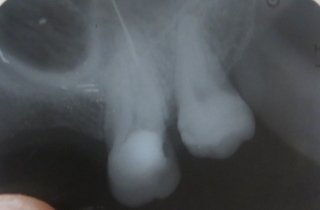

В подростковом возрасте мне сделали резекцию передних зубов из-за кисты. Но спустя примерно 15 лет над зубом образовался, на ощупь, шарик и очень неприятное напряжение под зубом. Я пошла к врачу, он отправил на снимок, но так и не смог мне помочь, и отправил к другому стоматологу, но попасть к нему я так и не смогла.

Вы не могли бы мне сказать, что это? И к кому мне нужно обратиться? У нас городок маленький и специалистов не так много.

У вас так называемый рецидив. Обратитесь к хирургу, думаю, данный зуб придется удалить.